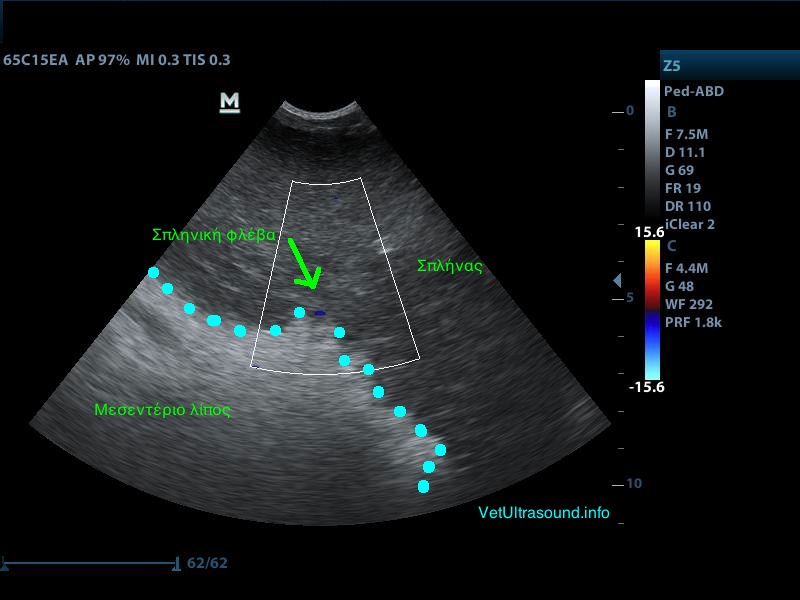

Διάγνωση: Ο σπλήνας ελέγχθηκε διογκωμένος και διάχυτα υποηχογενής χωρίς εστιακές αλλοιώσεις στο παρέγχυμά του. Το μεσεντέριο λίπος γύρω από αυτόν ήταν αρκετά υπερηχογενές και βρέθηκε μικρή παρουσία ασκιτικού υγρού ανάμεσα από τις εντερικές έλικες. Το έγχρωμο Doppler δεν έδειχνε αιμάτωση του σπλήνα και ιδιαίτερα των μεγάλων αγγείων. Η διάγνωση τέθηκε ως συστροφή σπλήνα και ο ασθενής οδηγήθηκε στο χειρουργείο.

– Το υπερηχογενές λίπος στην προκειμένη περίπτωση οφείλεται στην συστροφή των αγγείων και του λίπους με τη σειρά του στη πύλη του σπλήνα.

– Ο σπλήνας εμφανίζεται έτσι λόγω του οιδήματος που δημιουργείται από την παθητική συμφόρηση εξαιτίας του στραγγαλισμού των αρτηριών και των φλεβών που των αιματώνουν.